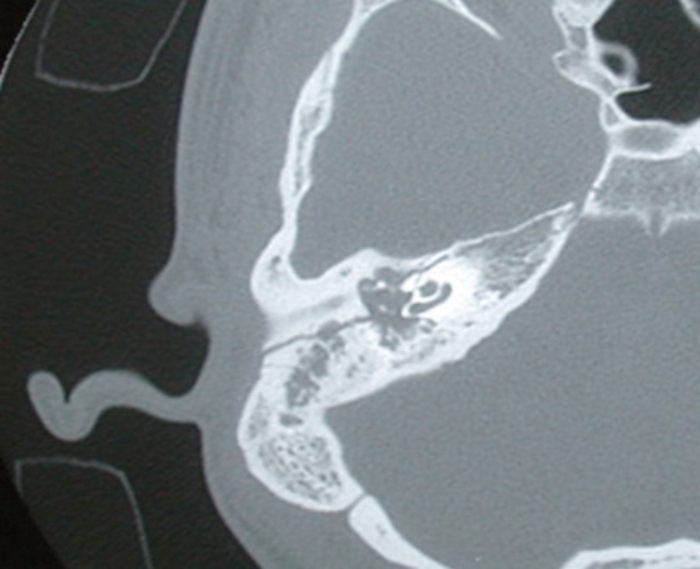

Figure1: Axial CT scan showing a longitudinally orientated fracture line running postero-superior

to the EAC and causing a haemotympanum and disruption to the ossicular chain.

Traditionally, fractures have been divided into transverse or longitudinal (Figures 1 and 2). Longitudinal fractures usually arise from lateral blows to the head, with the fracture line following the path of least resistance. Transverse fractures arise from blows to the occipital region. However, numerous studies demonstrated no prognostic value in this classification, with the incidence of true longitudinal fractures rarely occurring, rather an oblique fracture with features of both. More recently, the involvement of the otic capsule (more common in transverse fractures) has been used as a more relevant clinical descriptor, as this allows for the more accurate prediction of associated complications [3, 4].